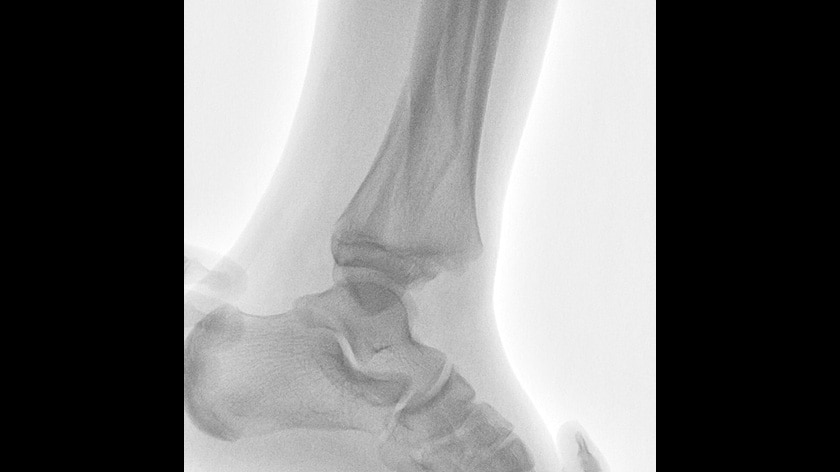

OPESCOPE ACTENO FD type, the mobile C-arm imaging system, provides free and easy positioning that achieves performance to meet the demands of the operation room and emergency room. The high-resolution FPD takes Surgical Imaging to new levels.

- Emergency/Trauma